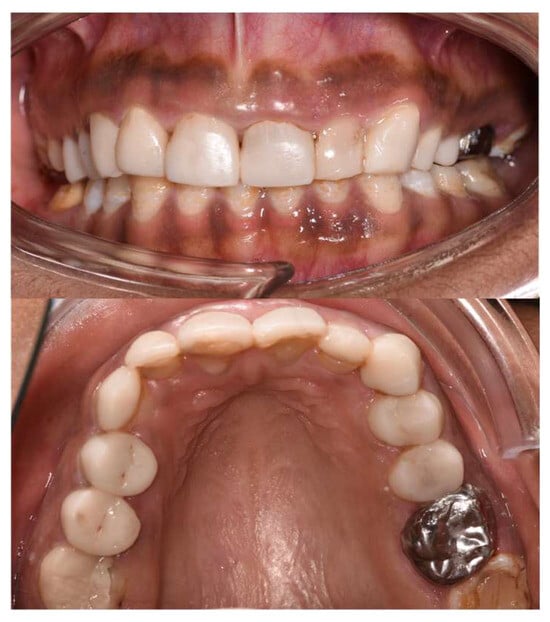

2.10.3. Eighth Session (Bonding)

2.11. Follow-Ups

2.11.1. At 15 Days

2.11.2. At 3 Months